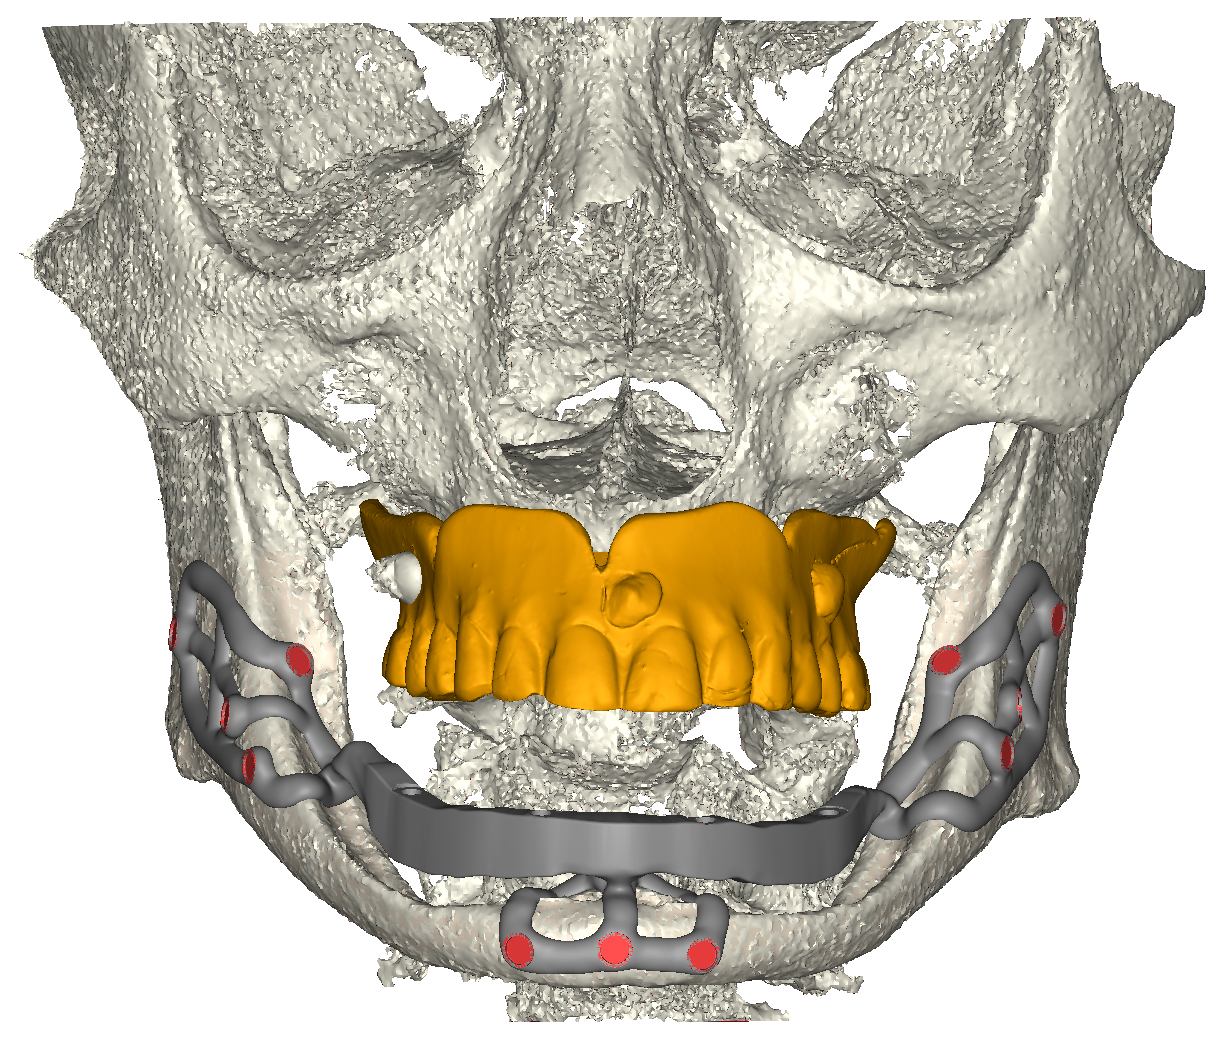

Il dispositivo prevede dunque tre punti di appoggio osseo stabilizzato a mezzo viti di sintesi (diametro 2 mm, lunghezza 6mm autofilettanti) e contestualmente tre emergenze, congiunte ad una barra extramucosa che funge da struttura di sostegno della contro-barra fresata rimovibile (fig. 3a, b, c), a sua volta ancorata ad attacchi a sfera. Contestualmente alla progettazione dell’impianto iuxta osseo, l’Odt. Fabio Marchiori, ha provveduto alla progettazione della parte protesica del dispositivo. Si è trattato, nello specifico, come appena descritto, di una controbarra ibrida: l’anima della struttura è stata progettata e stampata in titanio medicale (mediante tecnica SLM con Ti grado 23) e la componente anatomica è stata fresata da un disco di composito. La controbarra viene ancorata alla barra portante dello iuxta osseo per mezzo dei già citati attacchi a sfera, che sono stati avvitati per mezzo di filettatura dell’impianto stesso.

Vista frontale iuxta in posizione

Fig. 3(b). Vista frontale iuxta in posizione.